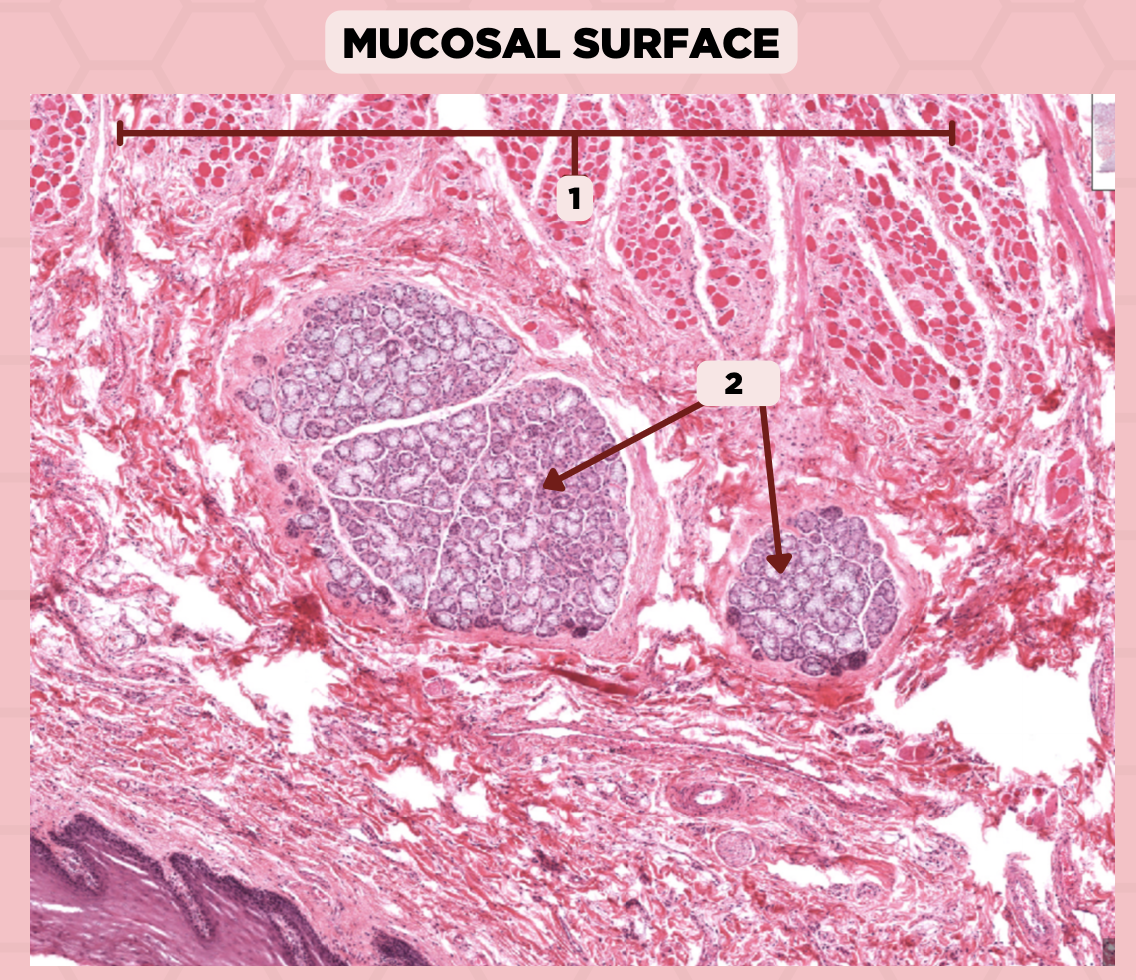

Parotid

Identify the specimen.

Capsule

Identify the structure labeled as 1.

Septa

Identify the structure labeled as 2.

Lobule

Identify the structure labeled as 3.

Lymph Node

Identify the structure labeled as 4.

Parotid

Identify the specimen.

Capsule

Identify the structure labeled as 1.

Lobule

Identify the structure labeled as 2.

Lobe

Identify the structure labeled as 3.

Connective Tissue

Identify the structure labeled as 4.